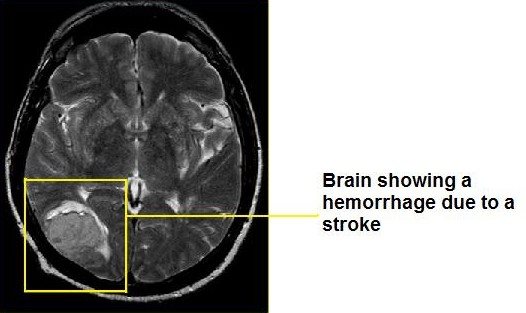

There are two types of stroke haemorrhagic and ischaemic stroke. Haemorrhagic occurs when there is a bleed due to a rupture and ischaemic occurs when an artery in the brain becomes blocked. Both these types of stokes can be caused by many factors including hypertension. The result of a stroke can be extremely disabling. Strokes are the UK's third biggest killer.

Image courtsey of https://upload.wikimedia.org/wikipedia/commons/f/f5/ACV_HEMORR%C3%81GICO.jpg.

Public domain image